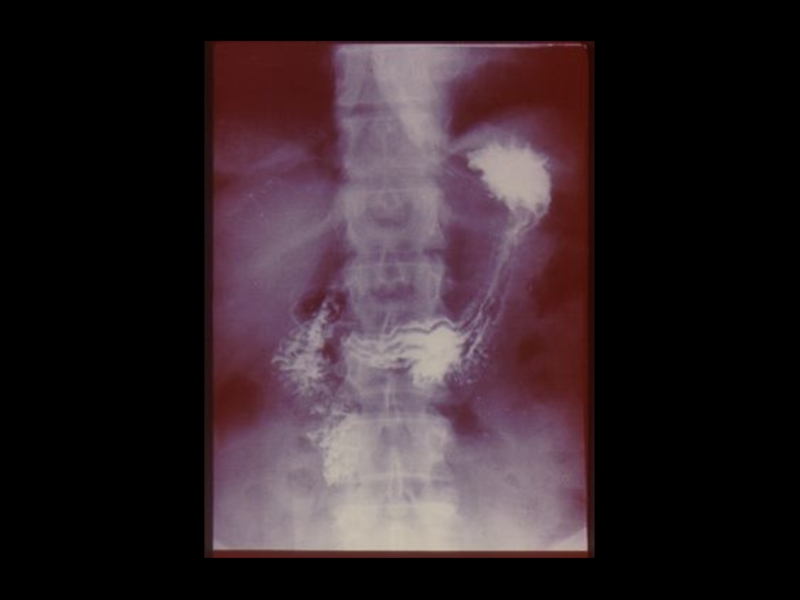

3. Специальные методы

(урография, бронхография, ангиография,

лимфография, пневмоартрография и другие)

Слайд 37Задачи искусственного контрастирования органов:

1. Получение изображения органов , не обладающих

естественной контрастностью

2. Повышение разрешающей способности методов, за

счет повышения качества изображения и создания

эффекта «усиления»

3. Осуществление контроля при проведении

интервенционных мероприятий, проводимых с

помощью лучевых методик.